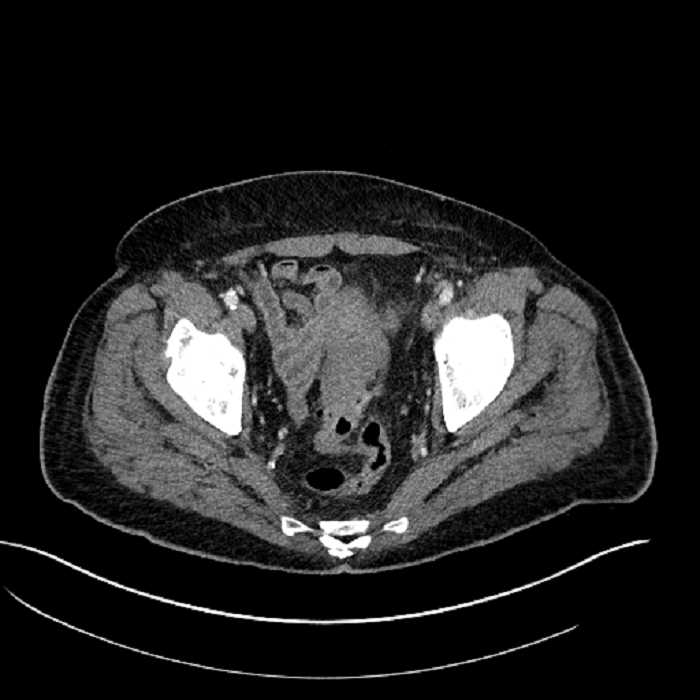

Age: 63

Sex: Male

Indication: Abdominal pain

• Mild mural thickening of a segment of the sigmoid colon with adjacent fat stranding and a 1.5 cm fluid and gas collection along the tip of an inflamed diverticulum

• Loss of the normal fat plane between this collection and adjacent loops of small bowel, which demonstrate mural thickening

• No bowel obstruction

• High grade stenosis of the left common iliac artery, with the left internal and external iliac arteries remaining patent

• Ankylosis of both sacroiliac joints

Acute sigmoid diverticulitis complicated by a small contained perforation and a large abscess in the right hepatic lobe. Additional small subcapsular abscesses along the anterior margin of the left hepatic lobe.

Additionally, loss of the normal fat plane between the peridiverticular collection and adjacent thickened loops of small bowel raises the potential for an enterocolonic fistula.

High grade stenosis of the left common iliac artery. The left external and internal iliac arteries are patent.

Hepatic abscess showing the double target sign with low density internally surrounded by a thin inner enhancing rim (red arrow) and ill-defined outer low density rim (yellow arrow). Blue arrow indicates an internal septation. Red arrows: additional smaller subcapsular abscesses. Red arrow: focal contained perforation associated with diverticulitis.